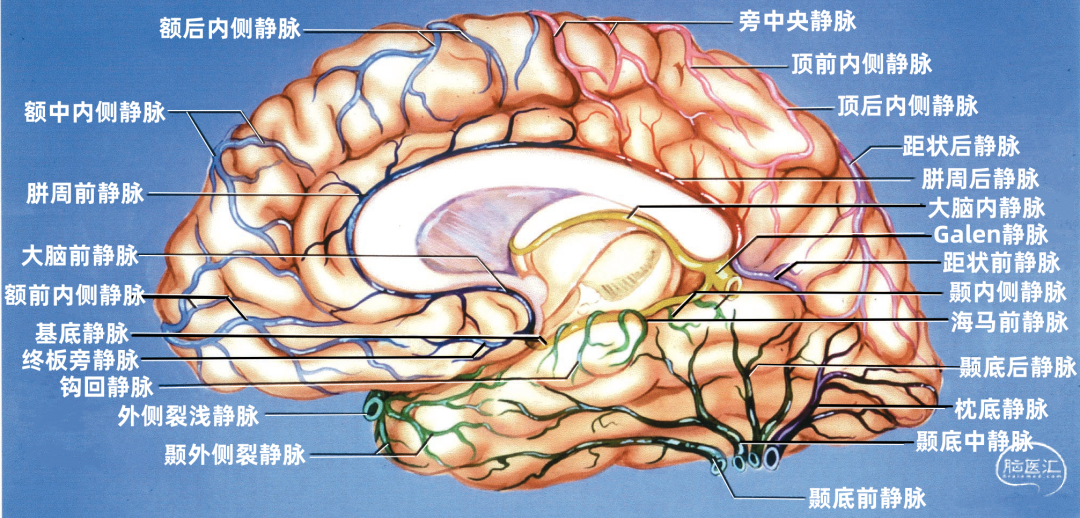

▼2.大脑内侧面静脉的引流区

额叶内侧面(蓝色)由终板旁静脉、额前内侧静脉、额中内侧静脉,额后内侧静脉、胼周前静脉、旁中央静脉引流。

顶叶内侧面(黄色)由旁中央静脉、顶前内侧静脉、顶后内侧静脉、胼周后静脉引流。

枕叶内侧面(紫色)由距状前静脉、距状后静脉引流。

大脑内侧面静脉的引流方向

额叶内侧面的静脉按引流方向由两种蓝色标出:浅蓝色为上升静脉,进入上矢状窦。深蓝色为下降支,汇入下矢状窦和大脑前静脉、基底静脉。

升支包括额前内侧静脉、额中内侧静脉、额后内侧静脉和旁中央静脉。降支包括终板旁静脉和胼周前静脉。

顶叶内侧面的静脉按引流方向由两种红色标出:浅红色为上升静脉,进入上矢状窦。深蓝色为下降支,进入Galen静脉及其属支。

升支包括旁中央静脉、顶前内侧静脉、顶后内侧静脉。降支为胼周后静脉。

枕叶内侧面的静脉按引流方向由两种紫色标出:浅紫色为上升静脉,进入上矢状窦。深紫色为下降支,进入Galen静脉及其属支。

升支包括距状后静脉和进入深静脉系统的距状前静脉。

额叶底面(蓝色)由额极静脉、眶额前静脉、眶额后静脉,嗅静脉和终板旁静脉引流。 颞叶底面(绿色)由颞底前静脉、颞底中静脉、颞底后静脉、海马前静脉、钩回静脉、颞内侧静脉、颞外侧裂静脉。

额叶底面的静脉按引流方向由两种蓝色标出:浅蓝色为前组静脉,进入上矢状窦。深蓝色为后组静脉,进入基底静脉前端。额底静脉的前组是眶额前静脉;后组包括眶额后静脉和嗅静脉。 颞叶底面的静脉按引流方向由两种绿色标出:深绿色标注的静脉向外侧走行汇入小脑幕窦。浅绿色标注的静脉向内侧走行汇入基底静脉。向外侧走行的颞底静脉包括颞底前静脉、颞底中静脉、颞底后静脉;向内侧走行的颞底静脉包括海马前静脉、钩回静脉、颞内侧静脉。 枕叶底面只有一支即枕下静脉,由紫色标出,汇入小脑幕窦。大脑内静脉汇入Galen静脉。

额叶的引流静脉分为外侧面组、内侧面组、底面组。外侧面组分为上升组,汇入上矢状窦;下降组,引流向外侧裂,进入外侧裂浅静脉。 上升组静脉包括额极、额前、额中、额后静脉,中央前静脉和中央沟静脉。这些静脉可能在回流至上矢状窦前与相邻的底面组、内侧面组的静脉汇合; 下降组由额外侧裂静脉组成。上升组引流的区域大于下降组。 额叶外侧面静脉及其引流区域如下:额极静脉引流额下回、额中回和额上回前部;额前、额中、额后静脉引流额极和中央前回之间的额叶前、中、后部凸面;中央前静脉引流中央前回下部、额下回盖部和邻近的额下、额中和额上回;中央Rolandic静脉引流中央沟附近的中央前回和中央后回;额外侧裂静脉引流额下回和邻近的额中回下部及中央前回下部。 额叶内侧面由弯曲的扣带沟分为内侧区和外侧区。额内侧静脉分为上升组进入上矢状窦;下降组进入下矢状窦或汇入行经胼胝体的静脉,最后进入基底静脉前端。上升组静脉由前内侧额静脉、中内侧额静脉、后内侧额静脉和旁中央沟静脉组成,它们是额上回内侧和邻近扣带回的主要静脉回流,一般向上弯曲走行,在半球上缘向外加入来自半球外侧组的静脉,然后注入上矢状窦。下降组静脉包括胼周前静脉、终板旁静脉和大脑前静脉。 额叶内侧面静脉及其引流区域如下:额前内侧静脉引流额极后方的扣带回和额上回;额中间内侧静脉引流胼胝体膝部前方的额上回和邻近扣带回的内侧面;额后内侧静脉引流胼胝体膝部上方的额上回和扣带回;旁中央静脉引流胼胝体体部上方的扣带回和邻近的旁中央小叶;胼周前静脉为成对的静脉,引流胼胝体膝部和嘴部,以及邻近的扣带回;大脑前静脉引流胼胝体嘴部以下至视交叉上缘之间的区域;终板旁静脉引流胼胝体嘴部下方的终板旁回和嗅旁回区域。 额下静脉组,引流额叶眶面区域,可分为前组和后组:前组流向额极注入上矢状窦;后组引流向后,在外侧裂内侧集中于前穿质表面,形成基底静脉。前组由额眶前静脉和额极静脉组成;后组由嗅静脉和额眶后静脉组成。 额下静脉及其引流区域如下:额眶前静脉引流直回前部和眶回前内侧部;额眶后静脉引流额叶眶面后部;嗅静脉引流嗅沟及其邻近的直回和内侧眶回。

顶叶的静脉根据引流分为顶叶外侧面组和顶叶内侧面组。 引流外侧面的静脉分为上升组和下降组。上升组汇入上矢状窦。下降组流入外侧裂静脉。上升组包括中央沟静脉和中央后静脉,还有顶前、后静脉。下降组由顶外侧裂静脉构成。 静脉及其引流区域如下:中央后静脉引流缘上回前部、顶上小叶和中央后回后部;顶前静脉引流缘上回和角回;顶后静脉引流顶下小叶后部和邻近的枕叶;顶外侧裂静脉引流中央后回和顶下小叶。 顶内侧静脉分为向上汇入上矢状窦的上升组和向下绕过胼胝体压部进入Galen静脉或其属支的下降组。上升组包括旁中央沟静脉、顶前内侧静脉和顶后内侧静脉。下降组为胼周后静脉。顶叶内侧面和外侧面的上升静脉经常在汇入上矢状窦前先在半球上缘汇合。旁中央沟静脉引流相邻的额叶和顶叶,与额内侧静脉一起描述。 顶内侧静脉及其引流区域如下:顶前内侧静脉引流扣带回上缘和楔前叶前部;顶后内侧静脉引流楔前叶后部和邻近的枕叶;胼周后静脉成对,引流胼胝体、扣带回和楔前叶后部。

颞叶静脉划分为:引流颞叶凸面的外侧组和引流颞叶底面的下组。 颞叶外侧组静脉还分为上升组,行向外侧裂。下降组,注入颞叶下方的静脉窦。上升组由颞外侧裂静脉组成,下降组由颞前、中、后静脉组成。 颞外侧静脉组及其引流区域如下:颞前静脉引流外侧面前1/3,颞上回除外;颞中静脉引流颞叶凸面中部;颞后静脉引流颞叶凸面后1/3,有时包括角回和顶叶前部;颞外侧裂静脉引流从颞极到外侧裂后端的颞上回。 颞下静脉分为:外侧组引流入小脑幕前外侧的窦;内侧组沿颞叶内侧缘,流入基底静脉。外侧组由前、中、后颞底静脉组成,颞底静脉好像放射状从枕前切迹发出,经过颞叶的下面。内侧组由钩回静脉、海马前静脉和颞叶内侧静脉组成。颞极附近基底面通常由颞外侧裂静脉引流。 颞下静脉及其引流区域如下:颞底前静脉引流颞底前1/3、颞枕回和邻近的海马旁回;颞底中静脉引流颞叶下面中1/3;颞底后静脉引流颞叶底面和枕叶前部;钩回静脉引流钩回和邻近的海马旁回:海马前静脉引流钩回后部和邻近的海马旁回;颞内侧静脉引流脑干上部旁基底池边缘的海马旁回。

枕叶的引流静脉分为外侧组、内侧组和底面组。引流颞叶和顶叶后部的静脉可引流枕叶前部。事实上,枕叶外侧面的引流静脉通常行向前方,而不是后方,这就使得在窦汇前方4~5cm的范围内没有枕叶外侧面的静脉直接引流入上矢状窦,枕叶内侧面后部同样如此。 枕叶内侧面由距状前、后静脉引流。距状前静脉(也称为枕内侧静脉)引流楔叶和舌回的前部,距状后静脉引流距状裂的后部。 枕叶底面由枕下静脉引流。枕基底静脉起自舌回下外侧部、邻近的颞枕区和颞下回连接的属支。它向前外侧走向枕前切迹,而且经常在注入小脑幕外侧窦之前与颞基底后静脉汇合。少数静脉向前内侧走行注入基底静脉。

从下表面引流入小脑幕窦的静脉包括颞底前静脉,颞底中静脉、颞底后静脉和枕底静脉。 内侧小脑幕窦接受来自小脑的静脉血流,并加入直窦。基底窦位于斜坡。 大脑镰组(上图 紫色)由直接或经由大脑内静脉、基底静脉和大脑大静脉汇入下矢状窦或直窦的静脉构成。汇入直窦的静脉(上图 紫色)或其属支,引流胼胝体附近部分的额叶、顶叶和颞叶内侧部,此组静脉的引流区域大致相当于大脑边缘叶,包括终板旁静脉,额眶后静脉、嗅静脉、胼周前静脉、胼周后静脉,钩回静脉、海马前静脉、颞内侧静脉和距状前静脉。

终板旁回和嗅旁回的静脉向后引流入大脑前静脉,并最终进入基底静脉前部。扣带回和胼胝体前部由胼周前静脉引流,可能汇入下矢状窦或大脑前静脉。扣带回后部由胼周后静脉引流,最后汇入四叠体池内的大脑大静脉或大脑内静脉。扣带回峡部附近和距状裂前部周围区域由距状前静脉引流,经过四叠体池汇入大脑大静脉或其属支。海马旁回的内侧部和钩回由钩回静脉、海马前静脉和颞中静脉引流,向内侧引流汇入脚间池和环池的基底静脉。 皮层浅静脉并不像通常所说的那样没有规律或变异极大,虽然大多数浅静脉并不沿脑沟走行,但依然可以帮助定位脑沟。 静脉和脑沟关系最密切的是:外侧裂浅静脉和外侧裂,中央沟静脉和中央沟,中央后静脉和中央后沟,顶前内侧静脉和扣带沟升支,顶后内侧静脉和顶枕沟,胼周前,后静脉以及胼胝体沟的前部和后部。在静脉汇入静脉窦的地方,它们与脑沟的毗邻关系变得就不突出了。 在不同的大脑,同一大脑的左右两侧,各皮层浅静脉的大小变异也比较大。大脑外侧面静脉比内侧面和底面的静脉粗大。大脑外侧面最大的静脉通常位于中央沟附近。 大脑外侧的静脉就像车轮的辐条一样排列,从外侧裂的主干向外辐射。皮层外侧三条最大的回流路径分别是Trolard静脉、Labbé静脉和外侧裂浅静脉。主要由Labbé静脉引流的例数,优势半球是非优势半球的两倍;而在非优势半球,Trolard静脉有类似比例。 事实上,牺牲某单支静脉并不经常造成静脉性梗塞、出血、水肿和神经功能障碍,这主要与静脉之间的吻合有关。相邻区域的皮层静脉、浅静脉、深静脉和脑池静脉之间存在丰富吻合支,在大脑半球外侧面、内侧面和底面的边缘也有许多吻合支引流邻近的部分。 在一些手术入路中,烧闭浅的桥静脉或深的桥静脉,包括大脑大静脉、基底静脉和大脑内静脉是无法避免的;但对于这些静脉及其属支的破坏应尽量减少,因为它可能造成严重的后果。另一种选择是仅切断一些小的属支,而将主干牵拉出术野。如果暴露时发现桥静脉较正常的粗大,手术时要尽量保留。 静脉增大提示其引流范围增大,损伤它们可能导致严重后果的几率增加。在一些病例中,粗大的Labbé或Trolard静脉或外侧裂浅静脉可能引流大脑半球外侧的大部。阻断由几条皮层静脉形成的桥静脉,较牺牲单个静脉末端形成的桥静脉或皮层支造成的后果要严重。